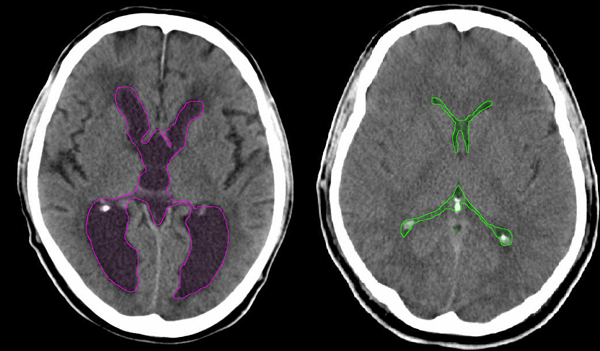

Αξονική τομογραφία ασθενούς με υδροκέφαλο αριστερά, με διάταση του κοιλιακού συστήματος (κόκκινο περίγραμμα). Σύγκριση με φυσιολογικό κοιλιακό σύστημα δεξιά (πράσινο περίγραμμα). |